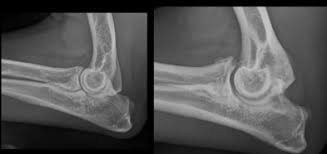

Elbows

dog elbow arthritis

Elbow arthritis may cause front-leg limping, especially after rest or exercise.